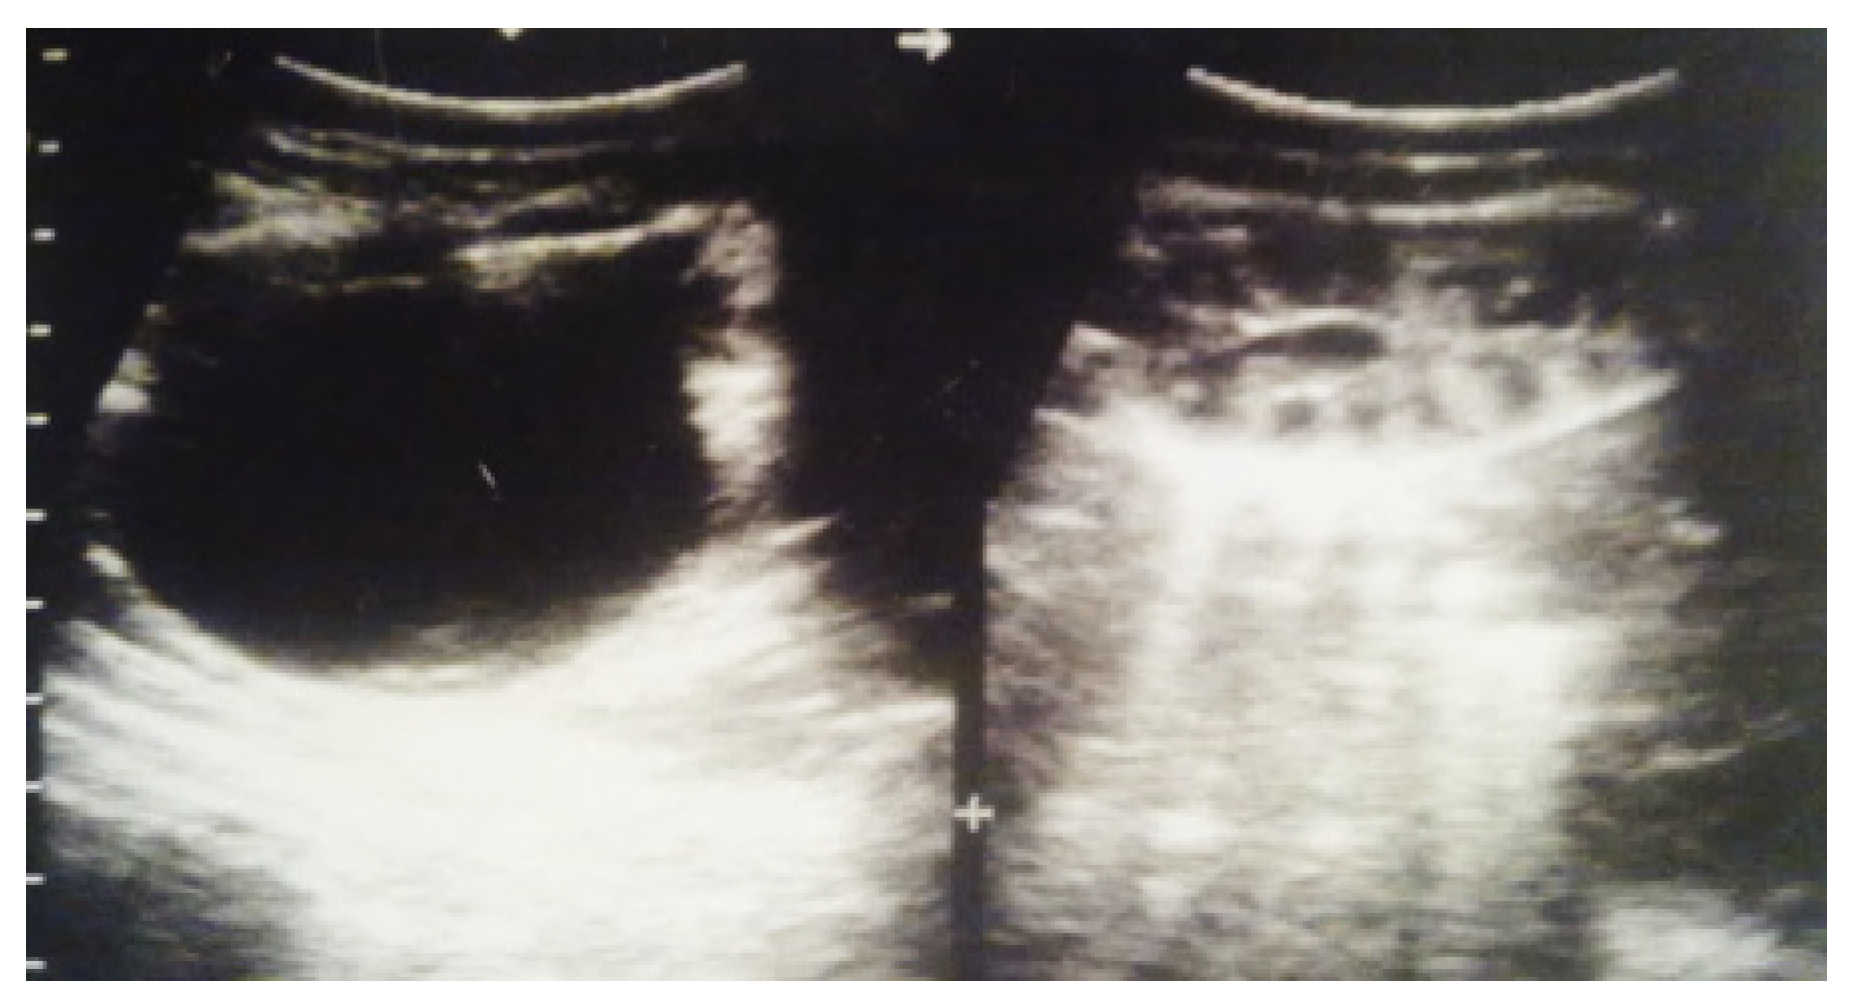

Our experience with congenital malformations of the urinary system refers to the following clinical case (Figure 2, Figure 3, Figure 4, Figure 5, Figure 6, Figure 7, Figure 8 and Figure 9). In the first case, during pregnancy, the 21-week ultrasound determined bilateral renal pyelectasia. The fetus had hydronephrosis on the right; at 31 weeks, it had bilateral hydrocalconephrosis; and at 32 weeks, bilateral pyelectasia. It suffered premature birth at 36 weeks, with complicated anomalies of the forces of contraction, prolonged birth, and birth weight of 2200 g. Postnatal ultrasonography was supplemented by intravenous urography, and bilateral hydronephrosis was determined. Hydrocalconephrosis on the left was discovered. The complete diagnosis was established: congenital renal malformation; bilateral pyelectasia; bilateral hydronephrosis; hydrocalconephrosis on the left; and severe reduced glomerular filtration rate (GFR), GFR > 2SD below mean.

Figure 4. Ultrasound at 31st week of gestation. Bilateral hydrocalconephrosis.

Figure 5. Ultrasound at 32 weeks of gestation. Bilateral pyelectasis.